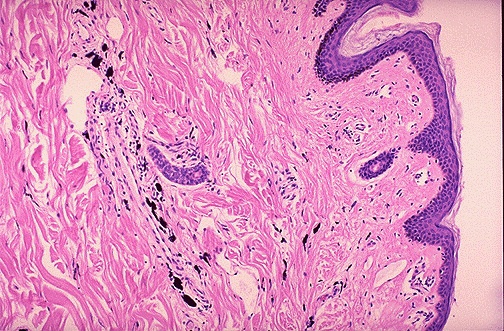

| This is the microscopic appearance of tattoo pigment (black) in the dermis. Note that this pigment is well within the dermis and, therefore, difficult to remove. Therefore, removing or changing a tattoo is difficult. Cosmetic surgery is not covered by insurance, either. |